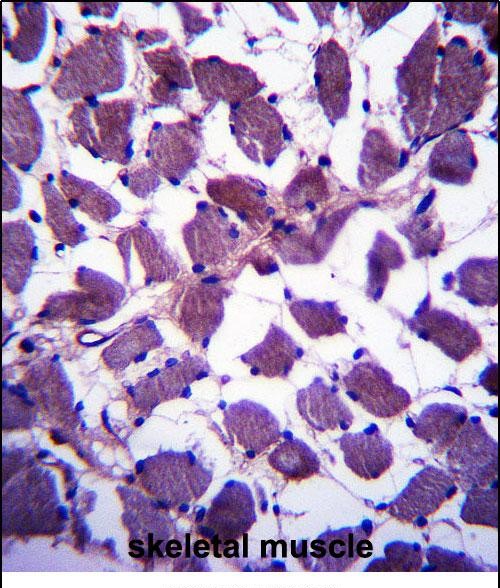

The HSPA12B (N-term) antibody is a specific reagent designed to detect the N-terminal region of the Heat Shock Protein Family A (Hsp70) Member 12B (HSPA12B), a less-characterized member of the HSP70 chaperone family. HSPA12B is distinct from other HSP70 proteins due to its unique structural features and tissue-specific expression, primarily observed in endothelial cells, the brain, and testis. It plays a role in cellular stress responses, protein folding, and maintaining cellular homeostasis, though its exact mechanisms remain under investigation. Studies suggest its involvement in angiogenesis, anti-apoptotic signaling, and protection against ischemic injury, linking it to cardiovascular and neurological disorders.

The antibody targets the N-terminal ATPase domain of HSPA12B, enabling researchers to study its expression, localization, and interactions via techniques like Western blotting, immunohistochemistry, and immunoprecipitation. Its specificity helps differentiate HSPA12B from other HSP70 isoforms, which share conserved regions but differ in function. Validation typically includes testing in knockout models or siRNA-mediated knockdown to confirm signal absence. Researchers utilize this tool to explore HSPA12B's role in diseases such as atherosclerosis, stroke, and neurodegenerative conditions, as well as its potential as a therapeutic target. Proper controls are essential to avoid cross-reactivity with homologous proteins.